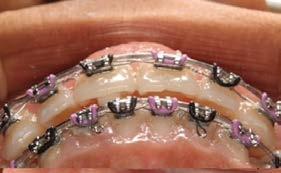

Objetivo: presentar un caso clínico de paciente con mordida abierta anterior, clase II y deglución atípica tratada con aparatología fija ortodóntica.

Caso clínico: paciente femenino de 19 años, patrón dolicofacial, perfil convexo, clase II esqueletal debido a una retrusión mandibular, mordida abierta anterior esqueletal, clase II molar, clase canina no establecida por mordida abierta, apiñamiento severo superior e inferior y deglución atípica.

Resultados: obtención de una clase canina I y clase molar II funcional, se corrigieron las sobremordidas horizontal y vertical, y se logró la coincidencia de líneas medias facial y dental. El manejo de la mordida abierta anterior se llevó a cabo por medio de la corrección del hábito de deglución atípica con la ayuda de spikes de resina, elásticos intermaxilares y arcos utility, y se obtuvieron buenos resultados estéticos, dentales y funcionales.